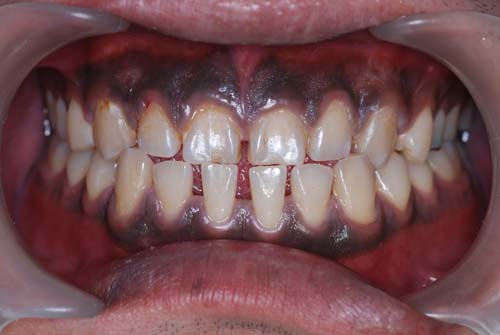

| これは重度の歯肉炎です。原因は多量の歯垢。ほとんど歯磨きをしていないと思われます。歯垢に触れている歯肉が赤くなっているのが分かりますか?炎症が起きており、少し触っただけで血膿が出、口臭もひどいです。歯肉がだいぶ弱っていますので、一番軟かい歯ブラシを使って歯垢を取ってください。歯肉のマッサージも少しずつやらないと健康な硬い歯肉には戻りません。 頑張ってください。 |

| 健康な歯肉です。色が全然違いますね。健康な歯肉は薄いピンク色なのです。 | ![]() |

| こちらの歯肉は黒いです。歯周病、歯肉炎は無いのですが、真っ黒です。喫煙者の歯肉ですが、タバコのヤニが直接沈着するのではなく、ニコチンやタールの刺激でメラニン色素が沈着するのです。いくら歯磨きをしても取れません。タバコを止めれば徐々に治っていきますが、かなり時間が掛かると思います。喫煙者は歯周病にも罹患しやすいので、タバコは止めるに越した事はありません。 | ![]() |